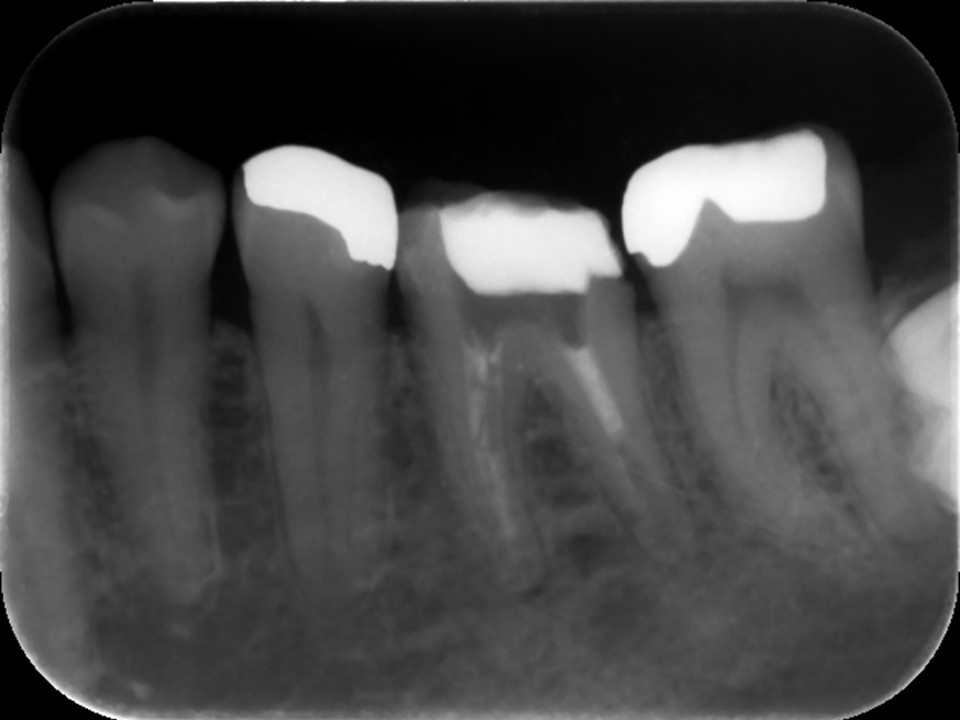

再根管治療後レントゲン。多少の違和感はあったものの、根管内部がきれいになり、排膿を認めないことから根管充填(薬を詰めること)を行った。根尖部までしっかりと薬が詰まっているのが分かる。歯根の内部がきれいな状態であれば、歯科医にはそれ以上出来ることはない。悪戯に弄り過ぎてはいけない。